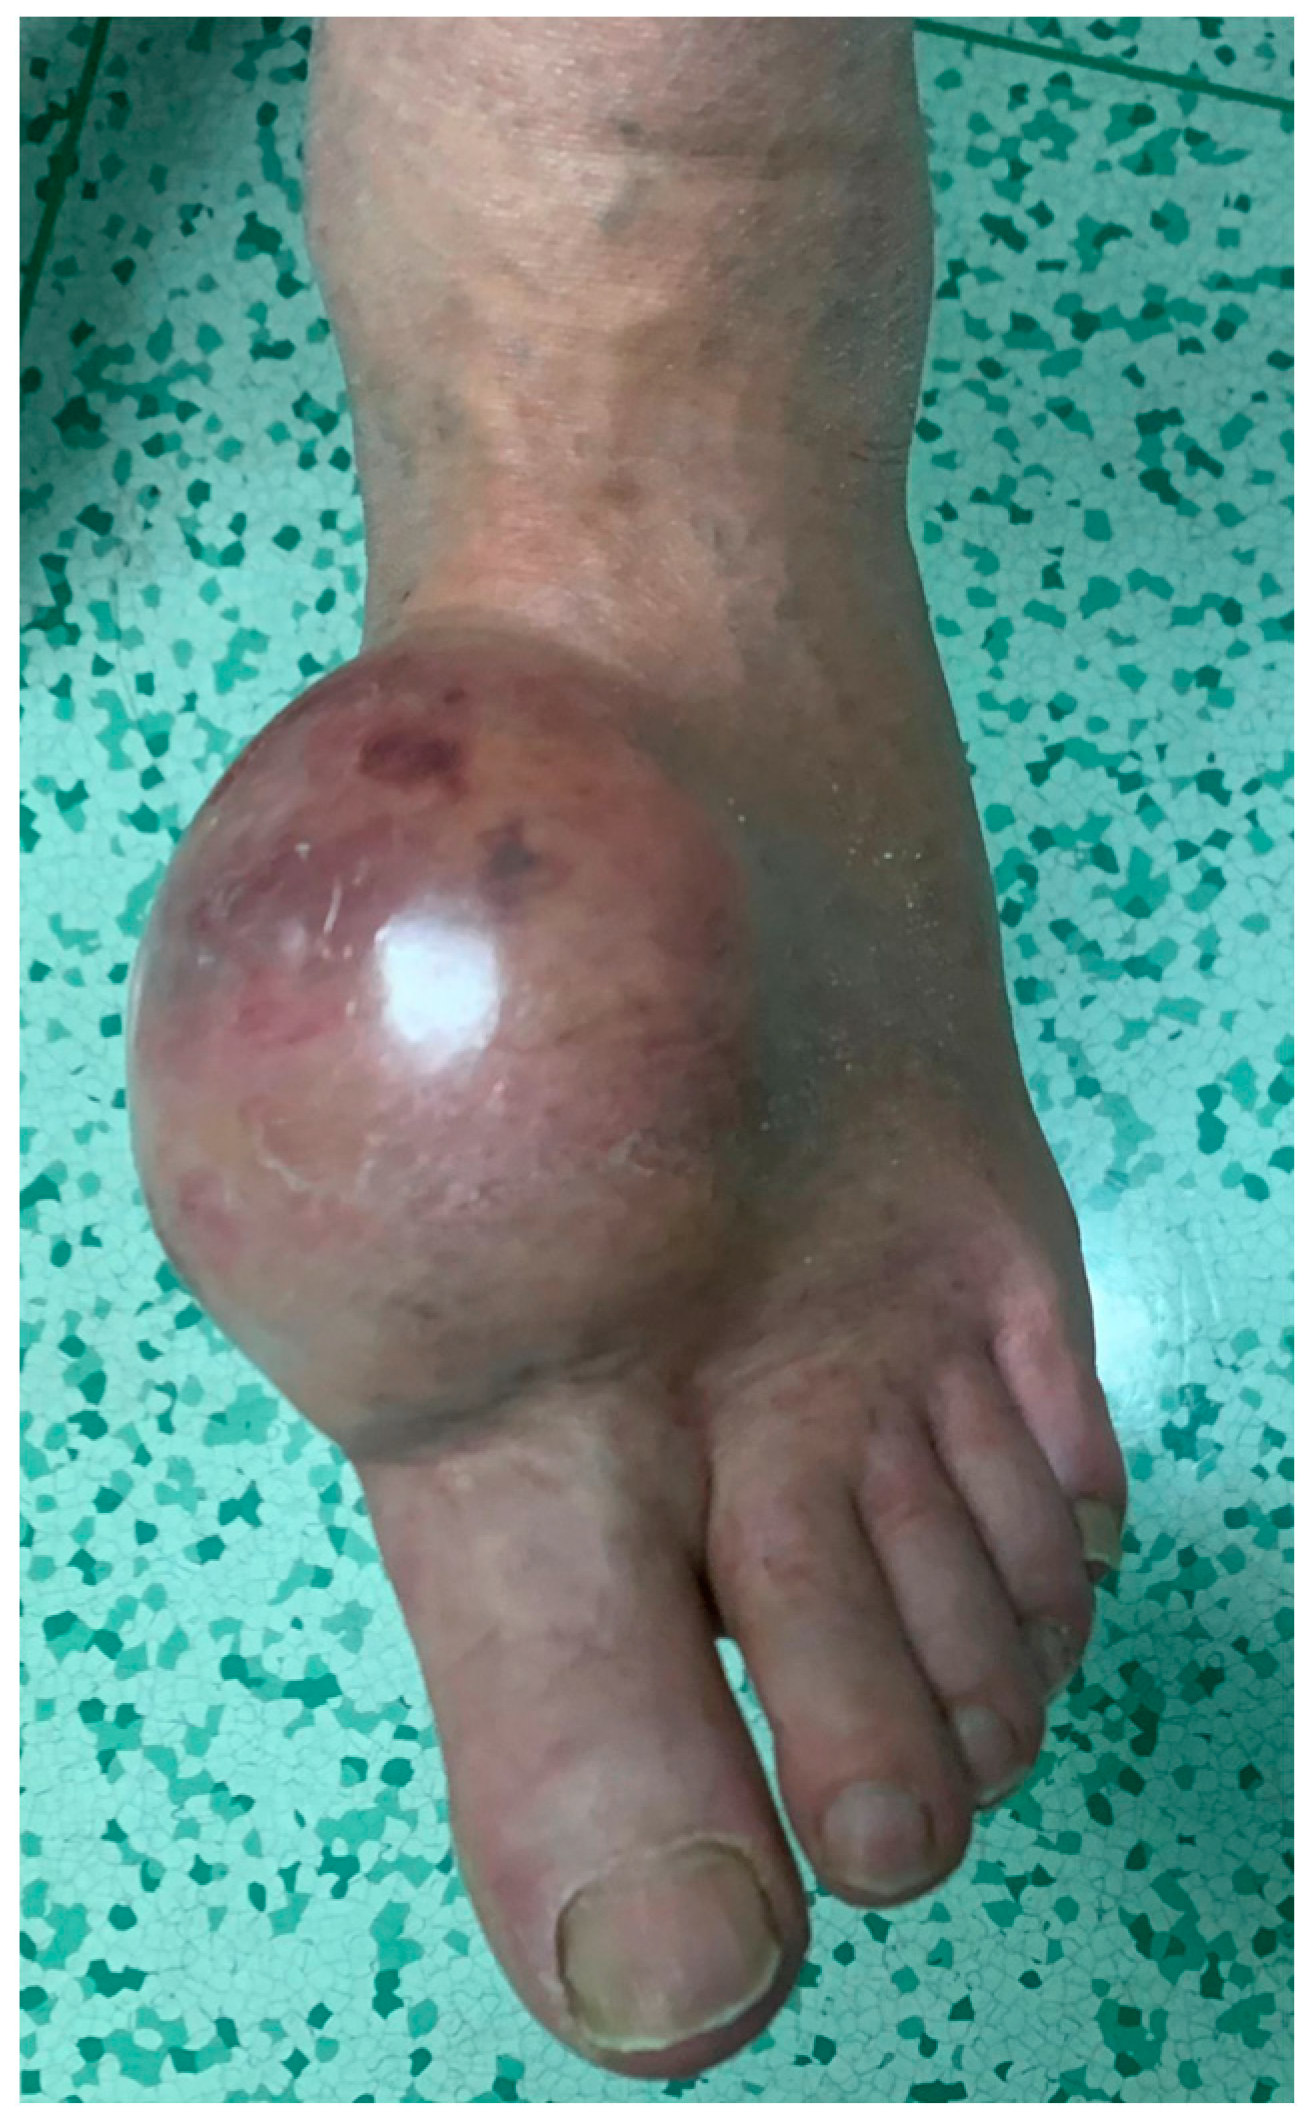

4.1. Melanoma

4.2. Epithelioid Sarcoma

4.3. Synovial Sarcoma

4.4. Clear-Cell Sarcoma

4.5. Rhabdomyosarcoma

4.6. Leiomyosarcoma

4.7. Liposarcoma